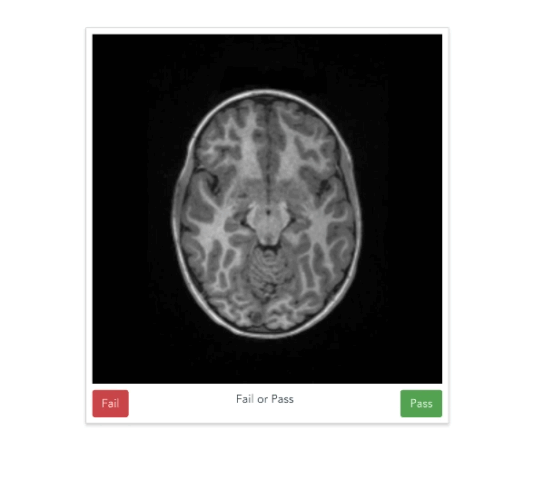

Scaling expertise with citizen science

Anisha Keshavan

Jason Yeatman

https://braindr.us

Multiple ratings per image

Aggregating across raters

XGBoost (Chen & Guestrin, 2016)

Scaling expertise using citizen scientist ratings